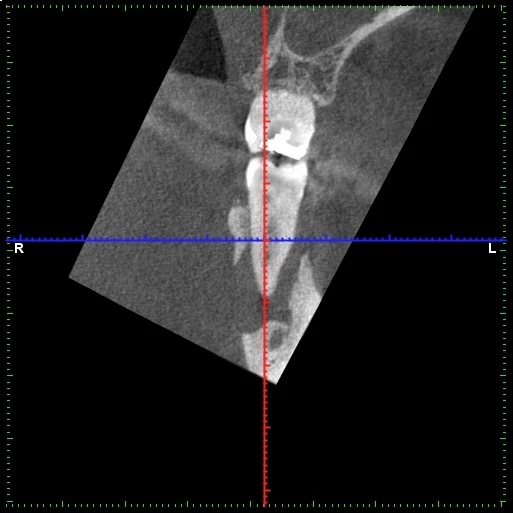

A menudo nos visitan en nuestra clínica dental de Terrassa pacientes con caries dentales avanzadas que necesitan un tratamiento de endodoncia para salvar sus dientes. La endodoncia es un procedimiento que trata el interior de la pieza dental y que permite mantener la dentición natural, el hueso y la encía que le rodea, así como su funcionalidad.